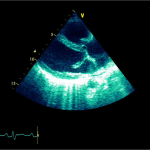

Ecocardiografia transtoracică

- Formaţiune hiperecogenă cu suprafaţa neregulată, care tapetează peretele liber al VD, grosime de 12 mm

- Dispusă de sub planul valvei tricuspide până in apropierea conului de ejecţie al valvei pulmonare

- SIV aplatizat

Ecografia transesofagiană:

Confirmă datele de la ecografia transtoracică